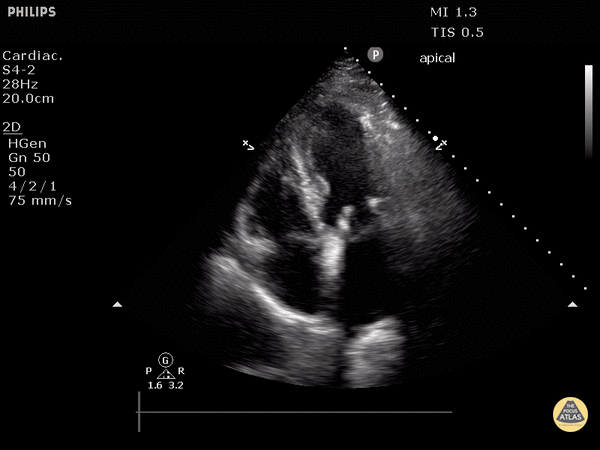

Valvulopathy - Prosthetic Mitral Valve (Apical 4 Chamber View)